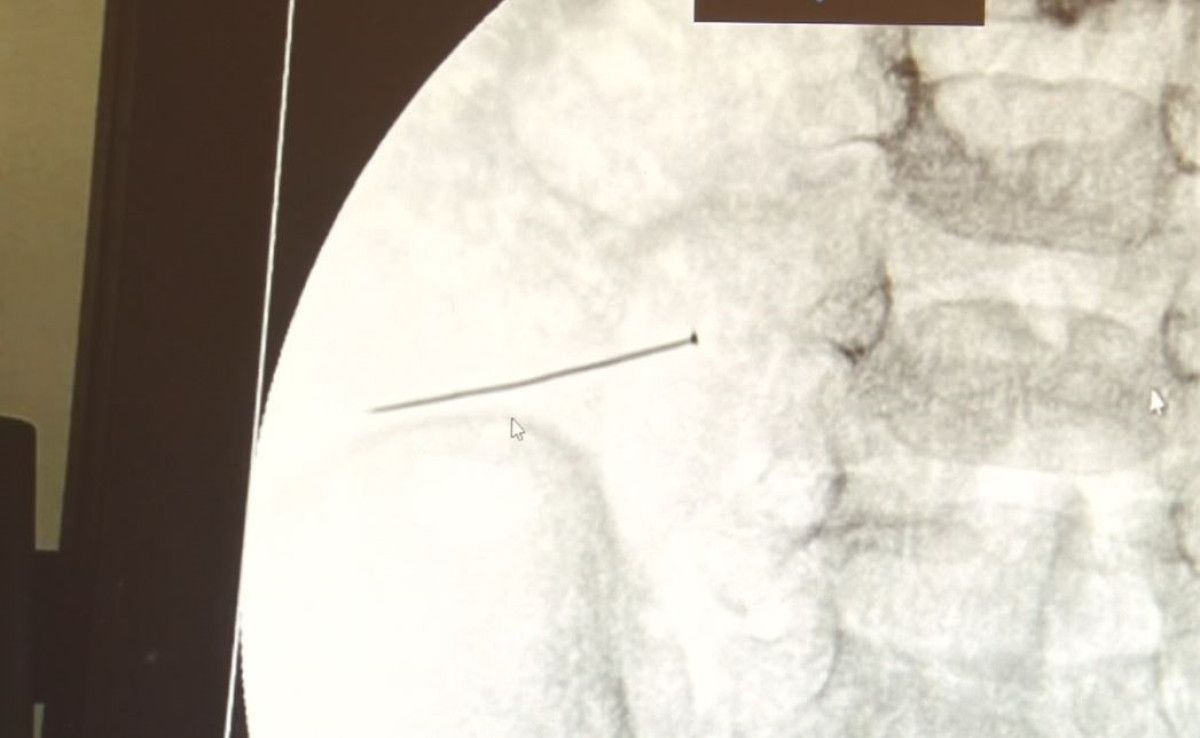

Türkiyədə 2 yaşlı körpənin bağırsağında 3 santimetrlik iynə tapılıb.

Müayinələr nəticəsində uşağın nazik bağırsağına təxminən 3 santimetrlik bir sancaq ilişib qaldığı və onu deşdiyi məlum olub.

Uşaq Cərrahiyyəsi Klinikasının Təhsil və İdarəetmə şöbəsinin müdiri Dosent Dr. Sefa Sağ və komandası 30 oktyabr axşamı dərhal əməliyyat ediblər. İynə uğurla çıxarılıb.